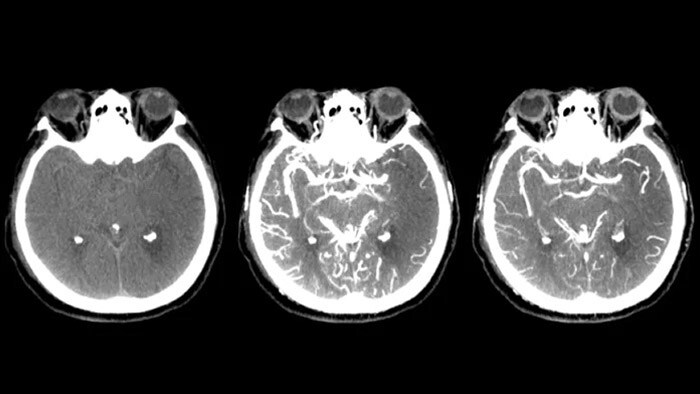

3D visualization beyond the clot

SmartCT Dual Phase Cerebral*

Offers acquisition of two consecutive contrast-enhanced CBCT scans of the brain, allowing identification of the vessel occlusion in the first phase and the presence of collateral vessels in the second phase.

SmartCT Vaso

Allows visualization beyond the clot with peri-procedural imaging of the distal vessel aspects in ischemic stroke. By retrograde filling, vessel structures before and after the clot become visible. The SmartCT Vaso 3D Roadmap can be used to visualize clot retrieval devices.